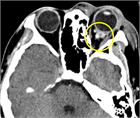

1. 造影CT(CTAngio)検査についてテキスト、画像を追加した。

1. 治療法に関し、ステロイドの投与、外科的視神経減圧術ついてテキスト、画像を追加した。